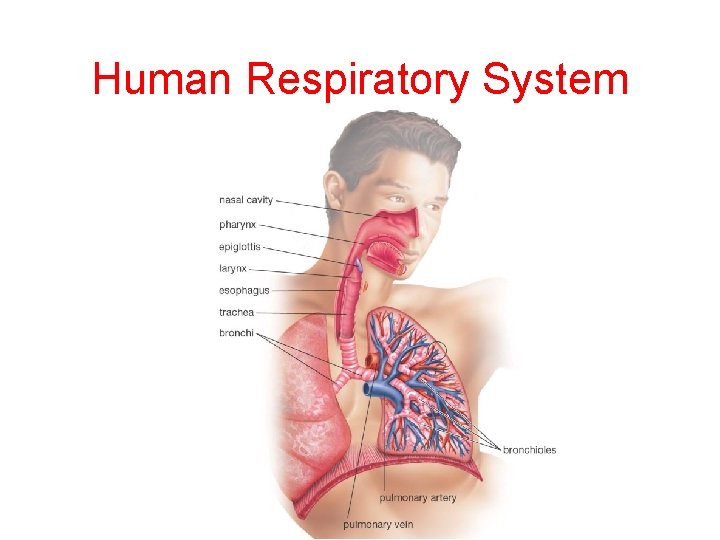

Human Respiratory System